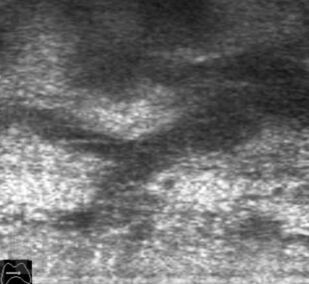

Ультразвуковое исследование оперированной щитовидной железы

В основу монографии положены материалы собственных исследований и практический опыт использования ультразвуковых методов диагностики при обследовании пациентов после хирургических вмешательств на щитовидной железе. Продемонстрированы диагностические возможности ультразвукового исследования в оценке состояния оперированной щитовидной железы в раннем и отдаленном послеоперационном периоде. Обобщена, систематизирована и представлена ультразвуковая семиотика зоны операции в ближайшие сроки после хирургических вмешательств и отражена динамика выявленных изменений. Убедительно показано, что ультразвуковое исследование может быть эффективным методом послеоперационного наблюдения.